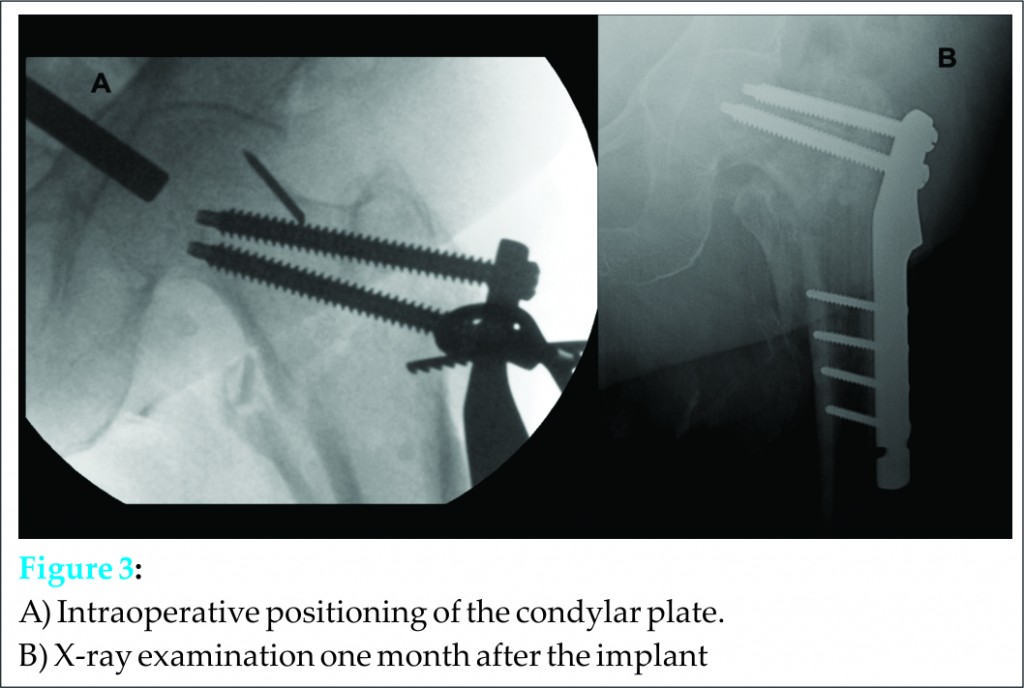

Several attempts with different surgical forceps were made to remove it through the screw hole, but the screw had penetrated deeply into the pelvis making it impossible to retrieve it. The general surgeon was called to perform an abdominal approach to remove the screw, which was finally retrieved in a few minutes without any further complications. Meanwhile, the procedure of osteosynthesis was completed using a condylar plate (Fig 3).